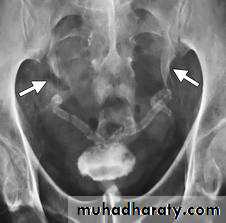

*Bilateral megaureter

*Bladder shistosmomiasis (calcification most important feature)